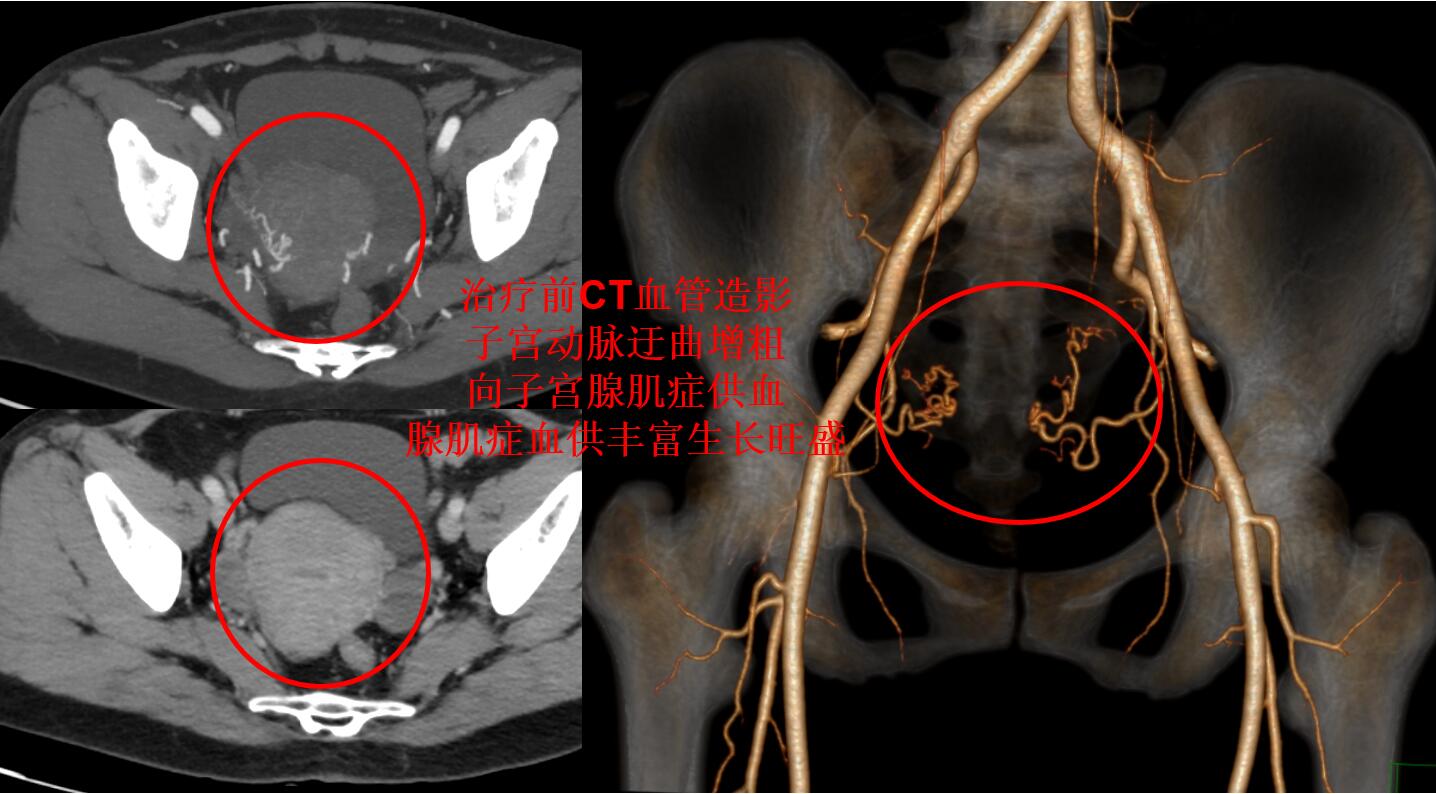

张女士,10年前已经出现痛经,痛经在可以忍受的范围,不用服用止痛药。由于心脏主动脉瓣钙化重度反流行心脏换瓣手术治疗,术后要一直服用抗凝药预防血栓。痛经问题就一直未处理。4年前痛经越来越厉害,卧床休息还是疼痛难耐,用止疼药止痛和中药调理,效果不好,到医院检查明确是子宫腺肌症引起的痛经。本来子宫腺肌症痛经有很多种治疗方法的,但是张女士做过心脏大手术并且要长期服用抗凝药,使得子宫腺肌症的治疗变得比较棘手,张女士也是因此一拖再拖。今年疫情,张女士子宫腺肌症痛经每月报到,还愈演愈烈,上医院打止疼针很麻烦,经病友推荐,来到广东省第二人民医院介入科就诊。张女士心脏大手术后用的抗凝药也是介入手术的常用药物,子宫腺肌症做介入治疗时可专业调控。由于张女士心脏手术换的是机械瓣膜,不能进行磁共振检查评估腺肌症状况,则用CTA评估显示:子宫腺肌症血供丰富,供血动脉迂曲增粗(如下图)。

通过CTA评估显示张女士的子宫腺肌症血供丰富,经大腿打针超选择栓塞子宫腺肌症的供血血管杀死腺肌症病灶会取得良好的疗效,则行子宫腺肌病介入超选择栓塞治疗(如下图)。